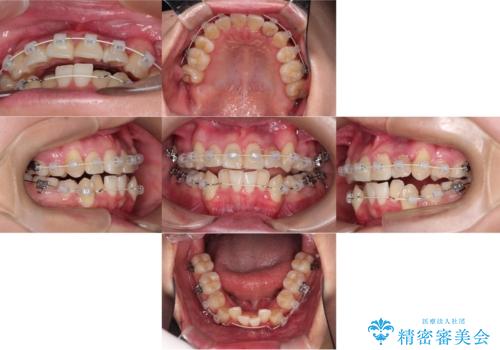

- 治療計画

- 「歯のでこぼこを治したい」を主訴に来院された患者様です。 上下ともに、歯のでこぼこが強く、上下左右4の抜歯をし、ワイヤー矯正で治療を行いました。

かなり綺麗に並ぶ事ができ大変満足していただけました。

叢生量がかなり多かったのですが、歯肉退縮も失活歯も無くとても綺麗な歯並びになりました。